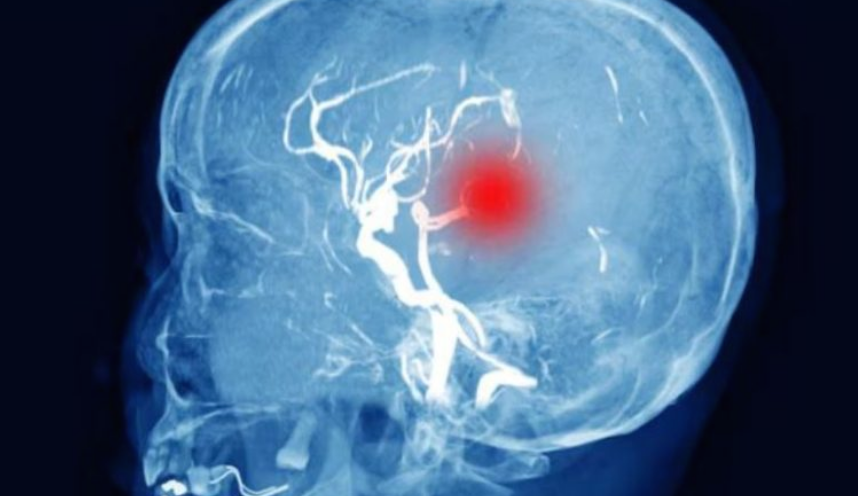

बीएचयू के न्यूरो सर्जरी विभाग में ब्रेन इंजरी के बाद मरीज की सीटी स्कैन रिपोर्ट। इसमें दिमाग में भरा पानी (काले रंग में) देखा जा सकता है।